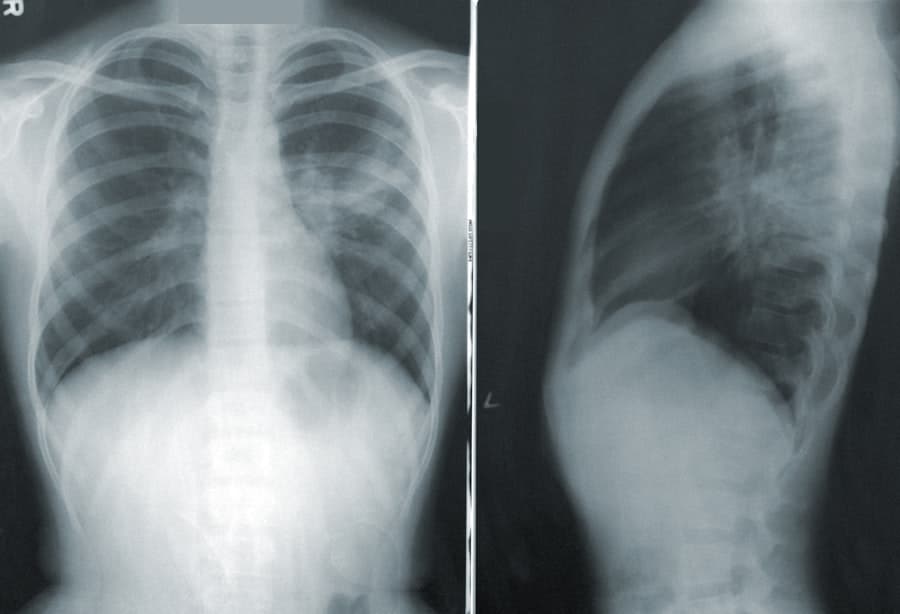

In some cases, imaging tests such as X-rays or MRIs may be necessary to visualize the structures within our lower back. These tests can help identify issues such as herniated discs, fractures, or signs of arthritis. By accurately diagnosing the underlying cause of our pain, we can work collaboratively with our healthcare provider to develop an effective treatment plan tailored to our specific needs.